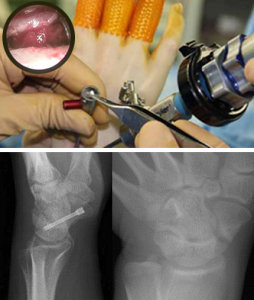

手関節鏡を用いた最小侵襲手術

上写真:術中写真

下写真左舟状骨偽関節 左:術前 右:術後

手関節鏡(2.3mmの内視鏡)を用いた低侵襲手術を行っています。従来の大きな皮切を用いた手術に比べて術後の疼痛が軽く、傷跡が目立たないのが特徴です。

【対象疾患】

- TFCC損傷

- 母指CM関節症

- ガングリオン

- 舟状骨偽関節 等